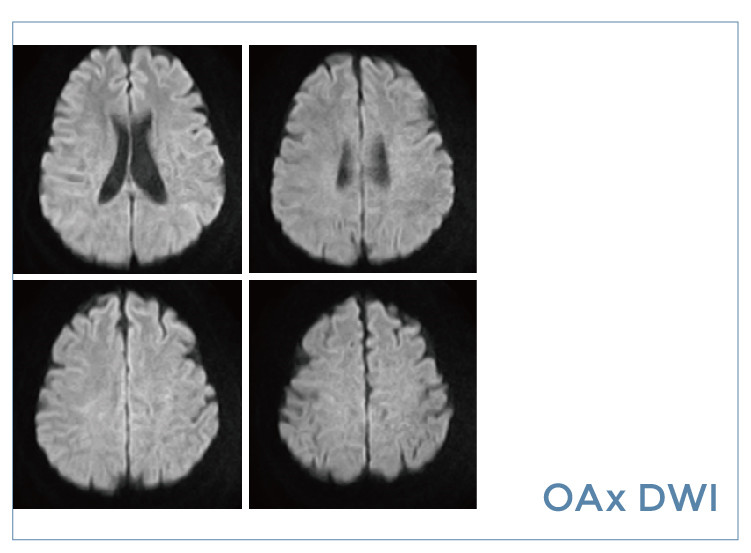

【朗润影像档案】磁共振影像病例分享(编号20190823)